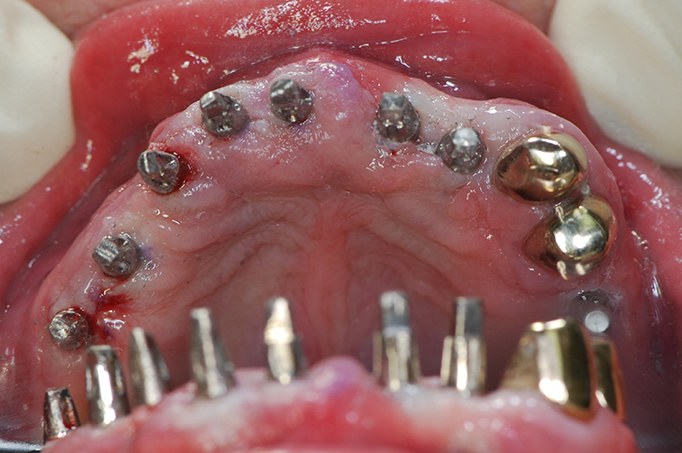

Sofortimplantate gleich nach der OP belastet - Nur zur Info - die Sofortbelastung wird bei uns aufgrund besserer Methoden nur noch selten angewandt .

Das vorbereitete Provisorium wird eingesetzt

Es gibt ein neues Verfahren, mit dem es gelingt ganz einfach Implantate zu setzten. Das Prinzip der Sofortbelastung, wie es bei den Hüftoperationen inzwischen routinemäßig durchgeführt wird, die Patienten gehen ja manchmal sogar am gleichen Tag auf eigenen Beinen, kann man auch auf die Zahnmedizin übertragen. Sofortimplantation wird nach wie vor in userer Praxis durchgeführt. Sofortbelastung wird jedoch nicht mehr angewandt, da es zu 4% Implantatverlusten statt bei verkürzter Wartezeit von 6 Wochen nur zu 1-2% Ausfällen kommt . Außerdem begünstigt die längere Einheilzeit die ästhetische Integration ins Zahnfleisch. In der Zwischenzeit bekommt der Patient jedoch ein Provisorium. Manchmal gelingt es auch ein herausnehmbares Provisorium zu vermeiden, indem man Zähne die zum Ziehen gelplant sind und langfristig nicht erhalten werden können, als Stütze für eine feste provisorische Brücke verwendet. Darunter können frisch eingesetzte Zahnimplantate ca. 6-8 Wochen fest einwachsen.

"Auch alle Zähne auf einmal lassen sich ersetzen. Wir bevorzugen viele Implantate zu setzten statt nur 4, da sich der Druck auf den Knochen besser verteilt. Knochen baut sich ab bei zu wenig Druck, aber auch bei Überlastung. Außerdem ist bei der Konstruktion auf nur 4 Pfeilerzähne im Falle eines Implantatverlustes immer die gesamte Konstruktion unbrauchbar.